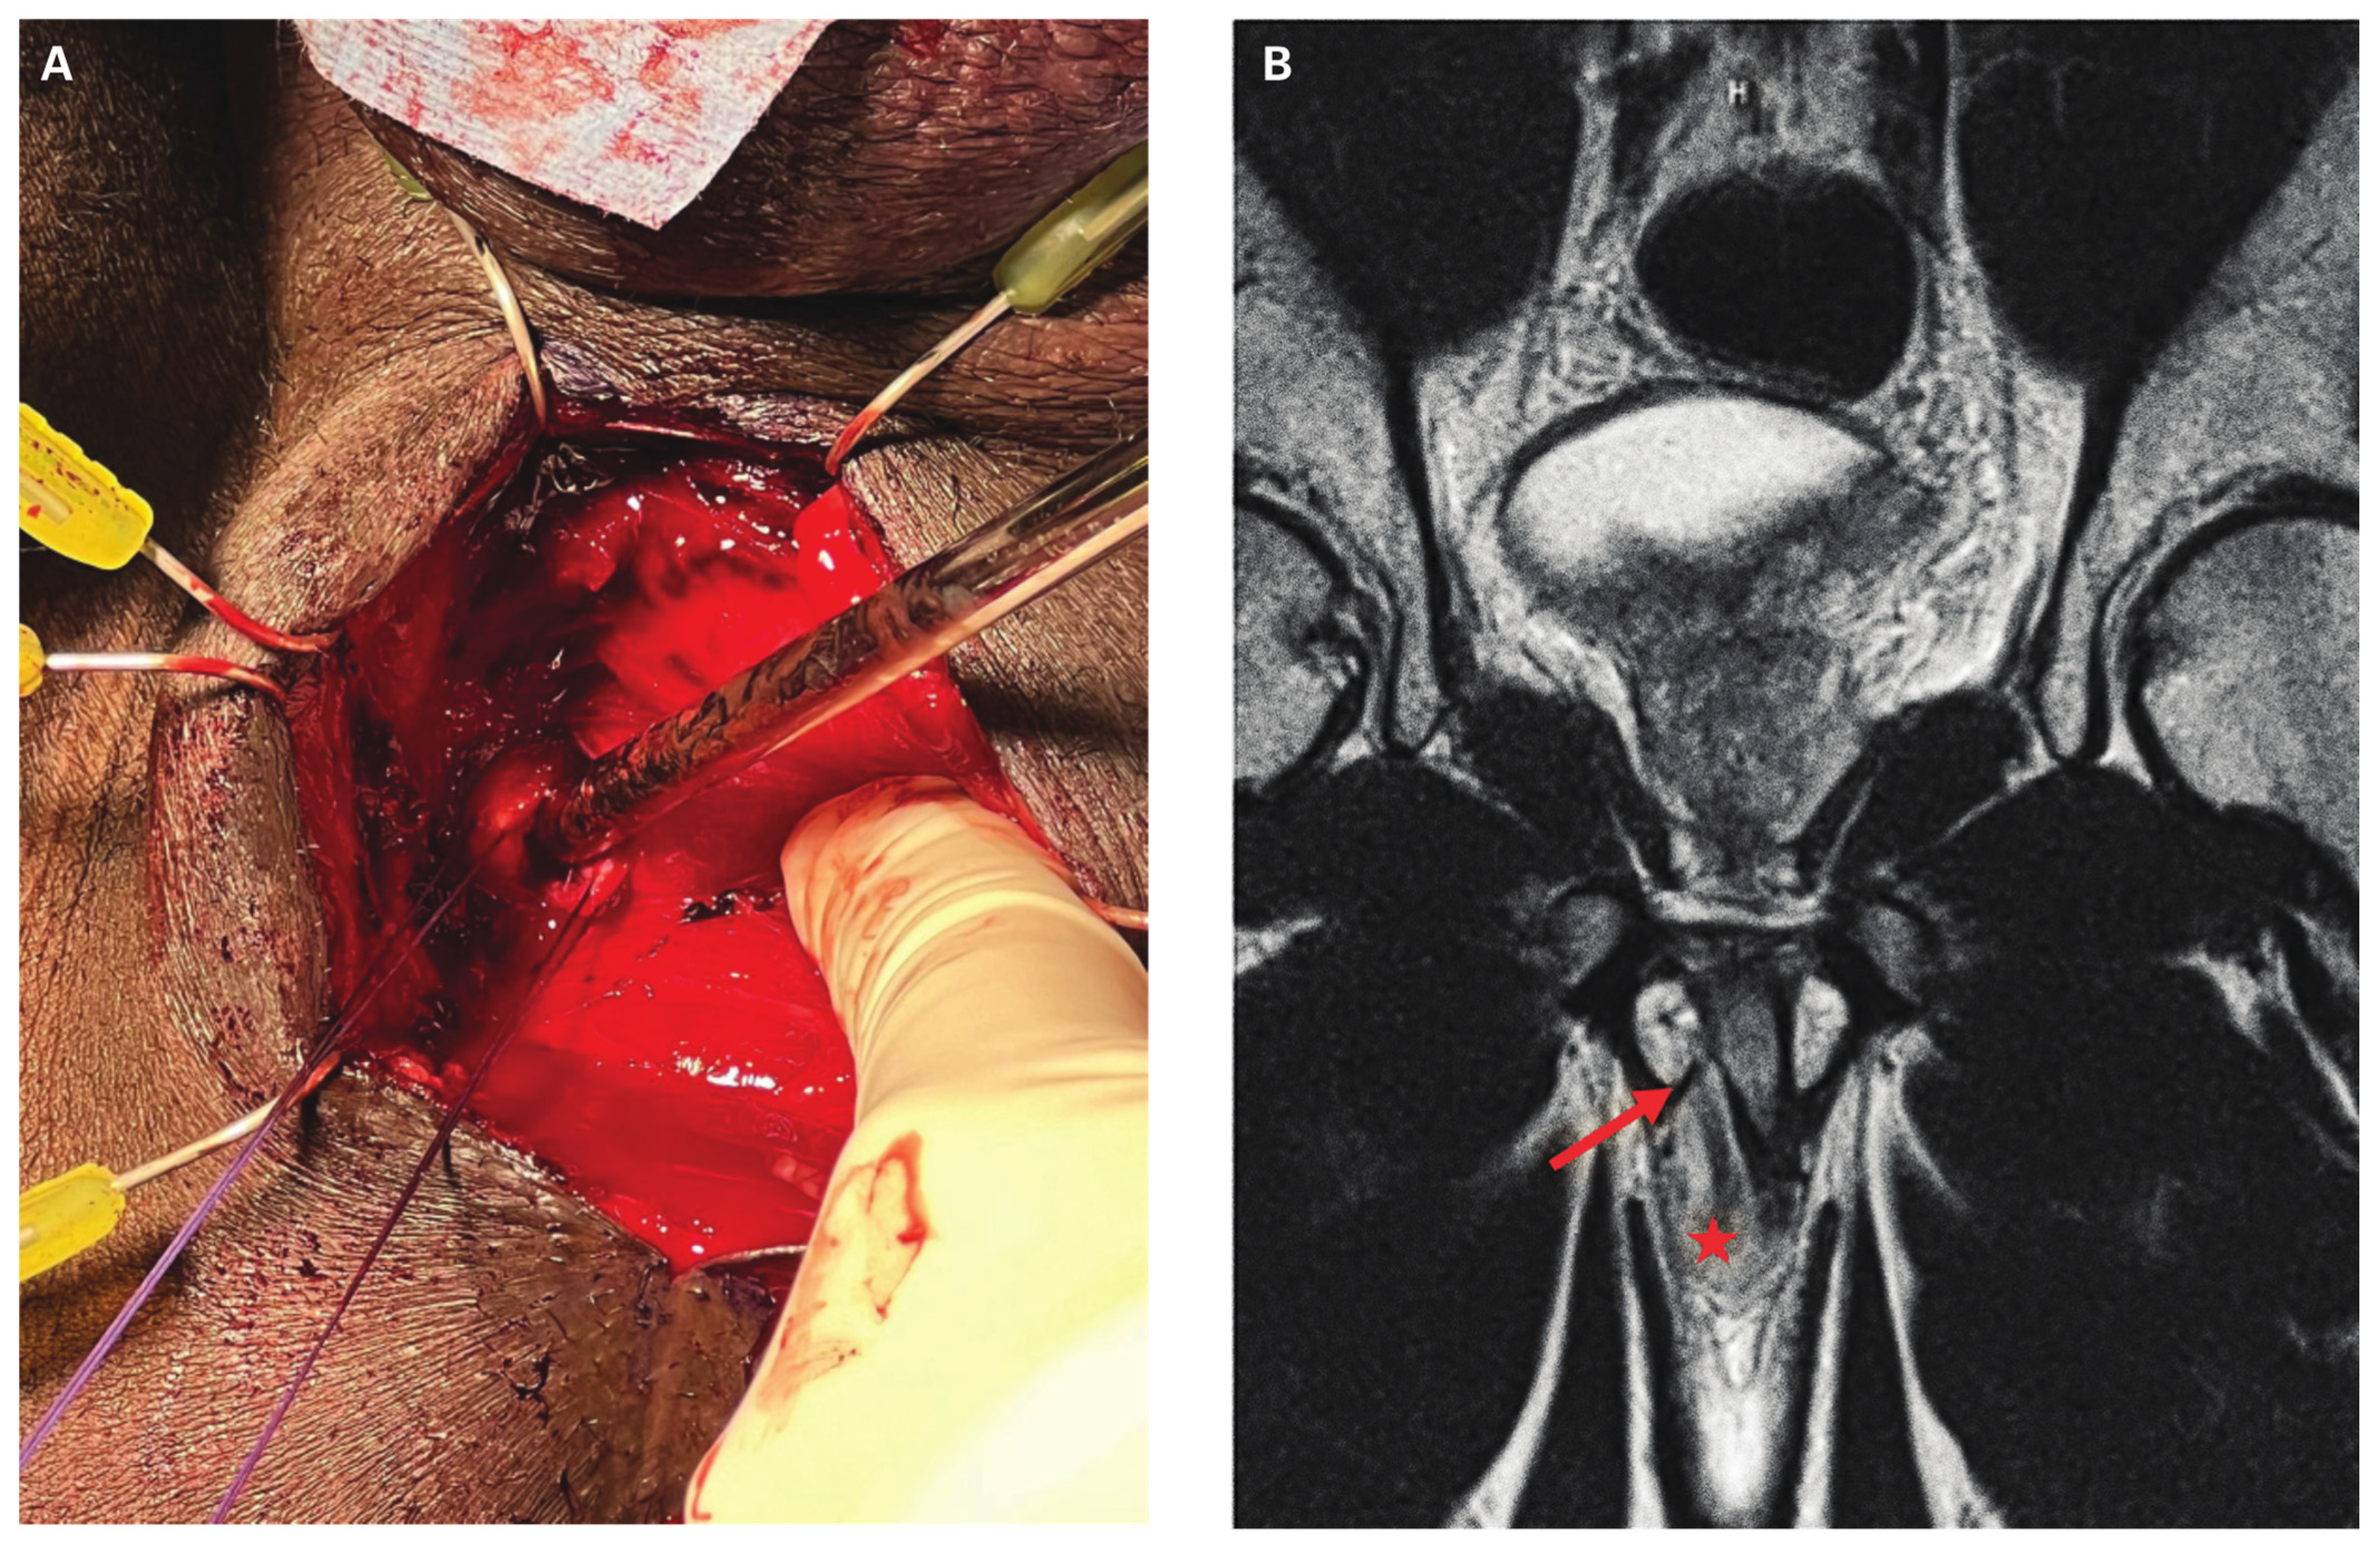

- Harada, J.; Shida, Y.; Gono, S.; Masato, M.; Yuno, T.; Hakariya, T.; et al. Rare case of penile fracture caused by an injury to the crus penis: delayed repair using the transperineal approach. IJU Case Rep. 2020, 4, 36–38. [Google Scholar] [CrossRef] [PubMed]